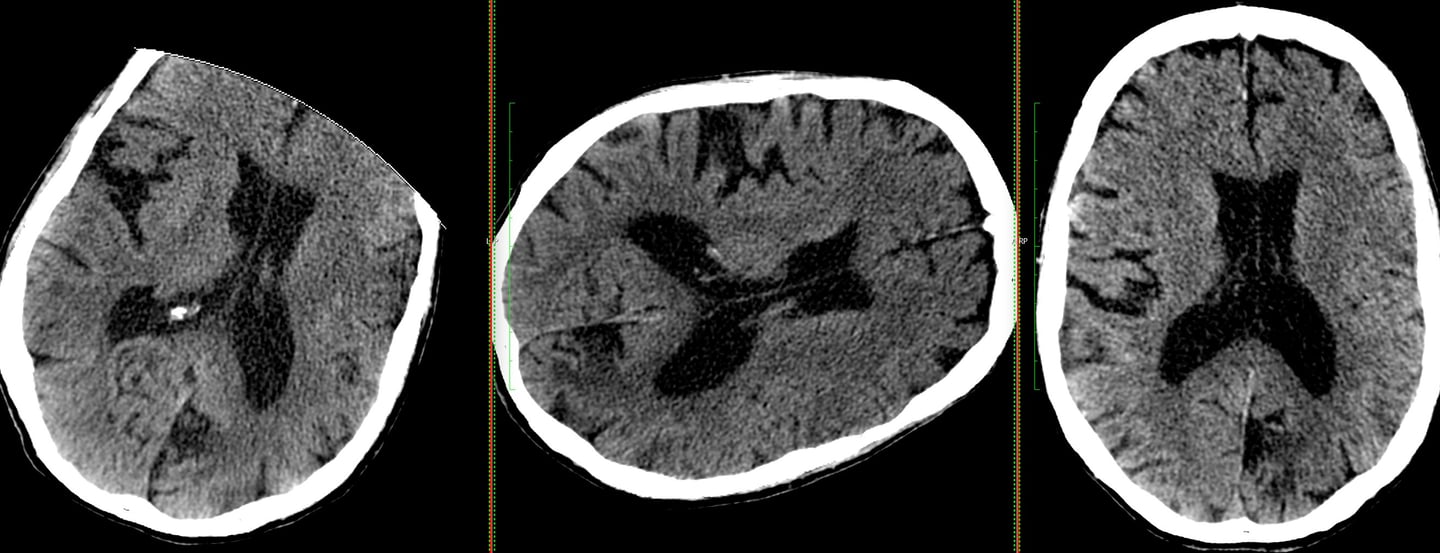

This 88 y.o. female was unable to fit into the scan circle due to severe kyphosis, so the tech put the patient on her side and scanned, allowing NeuroAlign to do the rest.